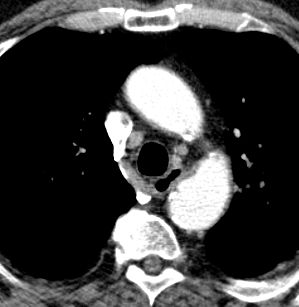

| Thoraxwanddestruktion | Plattenepithelkarzinom des rechten

Lungenoberlappens mit Destruktion der Thoraxwand und mediastinalen

Lymphknotenmetastasen. ![]() |